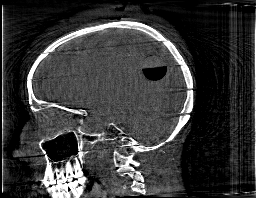

Krylov subspace methods are a powerful family of iterative solvers for linear systems of equations, which are commonly used for inverse problems due to their intrinsic regularization properties. Moreover, these methods are naturally suited to solve large-scale problems, as they only require matrix-vector products with the system matrix (and its adjoint) to compute approximate solutions, and they display a very fast convergence. Even if this class of methods has been widely researched and studied in the numerical linear algebra community, its use in applied medical physics and applied engineering is still very limited. e.g. in realistic large-scale Computed Tomography (CT) problems, and more specifically in Cone Beam CT (CBCT). This work attempts to breach this gap by providing a general framework for the most relevant Krylov subspace methods applied to 3D CT problems, including the most well-known Krylov solvers for non-square systems (CGLS, LSQR, LSMR), possibly in combination with Tikhonov regularization, and methods that incorporate total variation (TV) regularization. This is provided within an open source framework: the Tomographic Iterative GPU-based Reconstruction (TIGRE) toolbox, with the idea of promoting accessibility and reproducibility of the results for the algorithms presented. Finally, numerical results in synthetic and real-world 3D CT applications (medical CBCT and {\mu}-CT datasets) are provided to showcase and compare the different Krylov subspace methods presented in the paper, as well as their suitability for different kinds of problems.